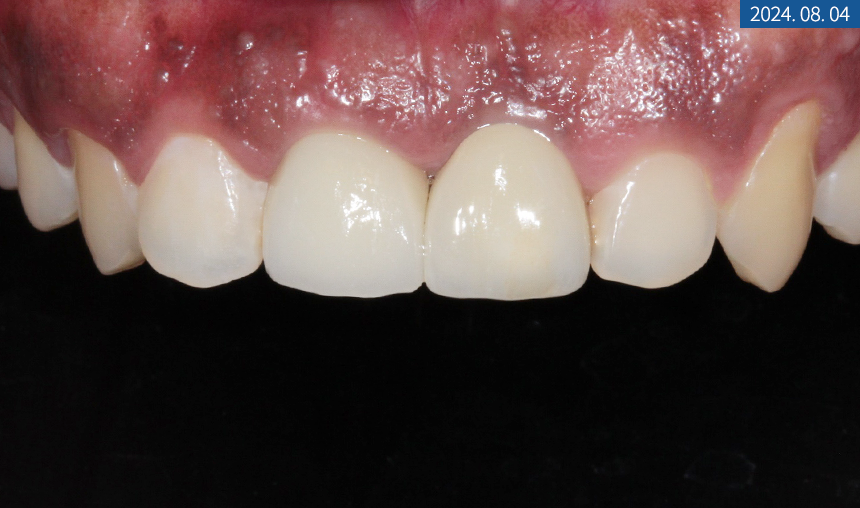

3개월 후 골 유착을 확인하고

교합과 인상 채득을 한 다음 크라운 제작을 위해

색상 대조 후 기공소에 의뢰했습니다.

2주 후 커스텀 어버트먼트와 크라운을

알맞게 체결, 수복해 드렸습니다.

한 달 후 치근단 사진을 찍어보니

주위 염증 없이 이식된 자리에

잘 위치하고 있었습니다.